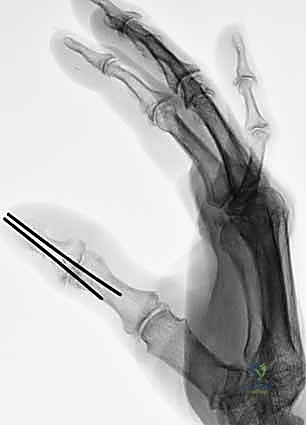

الأساس المتين هو أول خطوة في البناء. يقوم الدكتور هطيف بتقصير العظام قليلاً (Bone Shortening) لتخفيف الشد على الأوعية الدموية والأعصاب عند توصيلها. يتم تثبيت العظام باستخدام أسلاك كيرشنر المعدنية (K-wires)، أو مسامير دقيقة، أو صفائح معدنية صغيرة. التثبيت يجب أن يكون قوياً ليسمح ببدء العلاج الطبيعي المبكر.